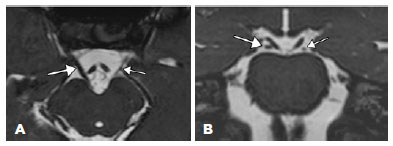

Multi-slice computerized tomography (Figure 2) was notable for marked left inferior rectus (LIR) and mild left superior and medial rectus muscle atrophy, with significant lipo-substitution detected in the region of the left superior rectus (LSR) muscle. Nuclear magnetic resonance imaging (MRI; Figure 3, 3 Tesla, high-resolution T2 sequence) demonstrated the hypoplasia of the third cranial nerve (CN III) which displayed decreased thickness compared to that on the contralateral side. The trochlear nerves were not adequately visualized. The other cranial nerves were of normal size.